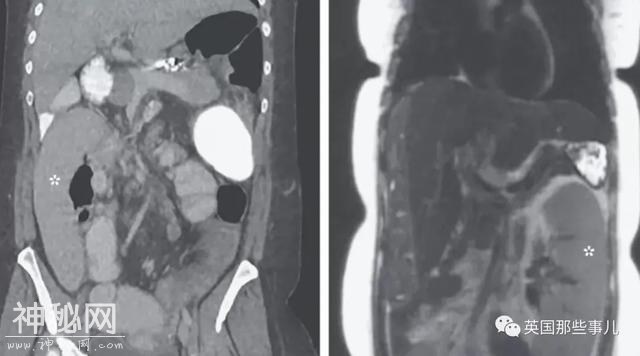

6,体内游走的脾脏

一名36岁的女性在密歇根医学中心做肝癌筛查,期间,医生给她的腹部拍了医学图像,当时脾脏在正常的位置。

一天后,该女子出现腹痛和呕吐,医生们重新做了扫描,发现她的脾脏竟然移动了0.3米,从左上腹部来到右下腹部。

绿尿,膀胱酿酒,心脏插针?2020年度诡异病例盘点,简直大开眼界-6.jpg

医生研究后发现,这是因为患者有硬化性胆管炎,其特征是将消化液从肝脏输送到小肠的胆管,发生炎症。

这种炎症会导致严重的肝硬化,堵塞管道,使血液回流,其中一个回流的地方就是脾脏。

随着时间推移,脾脏会越来越大,周围的韧带会被拉伸,使脾脏脱离位于上腹的正确位置。之后,脾脏就开始在身体内流浪。

解决这种病症的方法是摘除脾脏,患者之后开始准备切脾手术。